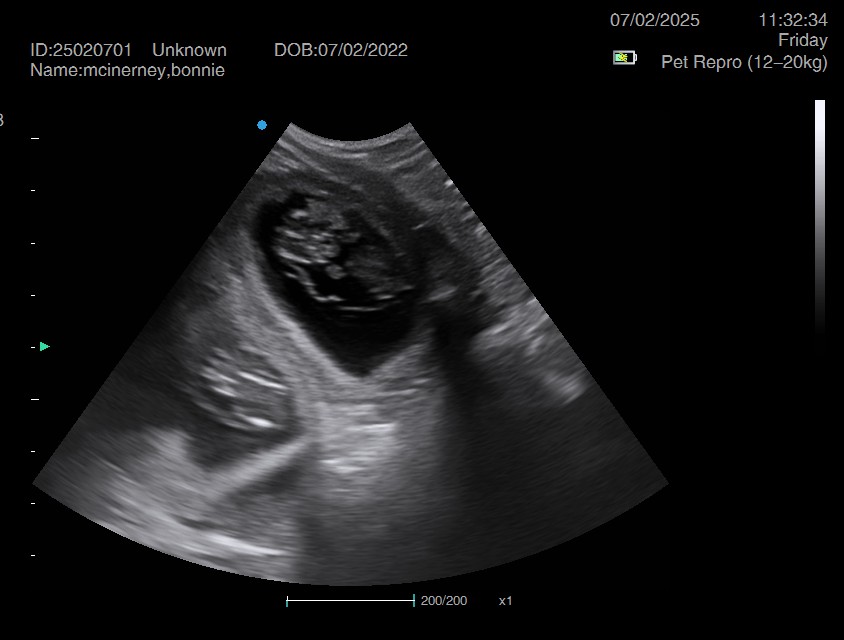

Ultrasound pregnancy scanning is a safe, non-invasive way to confirm pregnancy in dogs and cats, offering breeders and pet owners peace of mind and vital information to support responsible care. It allows us to detect gestational sacs, assess foetal development, and estimate litter size—all while ensuring the wellbeing of the animal.

Pregnancy can sometimes be detected as early as Day 18 post-mating, but scanning at this stage is not routinely recommended. Embryos are still developing and may not be clearly visible, and there is a natural risk of embryo resorption, which can lead to misleading or inconclusive results.

For the most accurate and reliable scan, we advise booking between Day 25 and Day 32, when pregnancy is more easily confirmed and foetal structures are clearer. If an early scan is performed and no pregnancy is detected, we offer a FREE complimentary re-scan after 7 days at the clinic to ensure clarity and support informed decision-making.

Our approach balances early insight with ethical care—always prioritizing the comfort of the animal and the accuracy of the results.